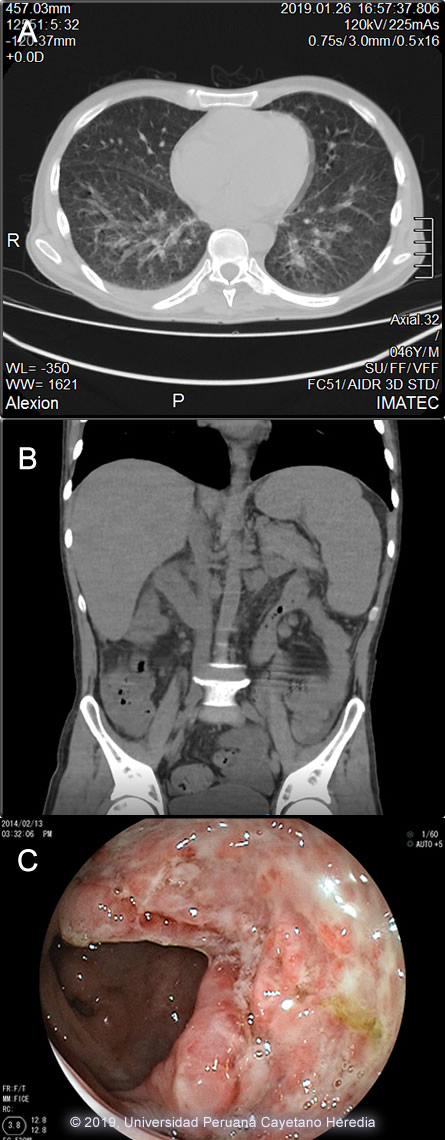

The chest x-ray showed bilateral interstitial infiltrates that were corroborated in the chest CT-scan [Image A]. An abdominal CT-scan showed visceromegaly [Image B]. A colonoscopy was performed, multiple colonic ulcers were observed scattered over the entire colon and ileum [Image C]. UPCH Case Editors: Carlos Seas, Course Director / Carlos McFarlane, Associate Coordinator UAB Case Editor: David O. Freedman, Course Director Emeritus / German Henostroza, Course Director |

![]() Discussion: A biopsy of a colonic ulcer showed a dense histiocytic infiltrate within the lamina propia. [Image D]. Multiple oval-shape intracellular structures measuring 3-4 microns compatible with H. capsulatum were identified in a Periodic Acid Schiff stain [Image E] and in a Grocott stain [Image F]. The differential diagnosis includes paracoccidioidomycosis where the yeast cells would be of different sizes and show multiple peripheral budding mimicking a pilot´s wheel, and visceral leishmaniasis; not endemic in Peru, you would expect to see a kinetoplast. Definitive diagnosis in these cases is made by fungal (bone marrow, blood or tissue culture lymph nodes, skin or oral lesions) as a gold standard, these results are pending. Cultures are positive in about 75% of patients [AJTMH 2013;89:937]. Urinary Histoplasma antigen is very useful (97% sensitivity) but usually not available in developing countries [PLoS Negl Trop Dis 2018;12(10):e0006802]. Direct observation of yeast cells from blood samples has low sensitivity (10%), better results are obtained from bone marrow samples. H. capsulatum is a dimorphic endemic fungus of worldwide distribution but is most common in North America and Latin America. In highly endemic areas more than 80% of persons are infected by age 20, often sub-clinically. Bats, which often live in caves, are frequently infected. Acquisition is inhalational with principal sites of disease in lungs, lymph nodes, liver, spleen, bone marrow, adrenals and the GI tract. Histoplasmosis is endemic in Latin America including Peru, the fungus is predominantly found in jungle areas. The reported incidence among advanced HIV-infected patients varies from 8% in Panama to 42% in French Guyana, being the first or second opportunist infection in these patients [AIDS 2016;30:167]. A necropsy study of 16 patients who died with advanced AIDS in Lima, Peru found that 3 (19%) had disseminated histoplasmosis [Pathol Res Pract 2006;202:767]. Exogenous acquisition or reactivation of a latent foci, as in this case are the modes of acquisition. Histoplasmosis is the most common endemic mycosis among HIV-infected patients. Progressive disseminated histoplasmosis (PDH) as demonstrated by this patient is the most common manifestation of histoplasmosis in AIDS patients. PDH may be the first manifestation of advanced AIDS in endemic areas, a study among 89 patients with advanced AIDS in Colombia found 45 (51%) with PDH [AJTMH 2016;95:918]. Predictors of PDH were significant weight loss, hepato or splenomegaly, skin lesions and hematologic abnormalities (mainly pancytopenia), many of them seen in this patient. Pulmonary involvement is seen in about 50-70% with non-specific manifestations (dry cough, chest pain, dyspnea); 50-70% of patients have abnormal radiologic findings; diffuse interstitial infiltrates or reticulonodular infiltrates are the most common abnormal findings. PDH is associated with high mortality rates, a study among 101 confirmed cases in Guatemala found a crude mortality rate of 44% with a median survival time of 19 days [AJTMH 2017,97:42]; a Peruvian case series from a single center found that 59% (16) of 27 HIV-infected patients with histoplasmosis had PDH, with a mortality rate of 22% [Rev Chilena Infectol 2017;34:365-9]. Chronic diarrhea is a common clinical presentation among HIV-infected patients. A long list of potential causes includes bacteria, viruses, parasites, fungi and malignancies. A study conducted in Peru among 147 HIV-infected patients showed that Cryptosporidium sp. Giardia lamblia and bacterial agents were the most common etiologies of persistent-chronic diarrhea [J Infect Dis 2005;191(1):11, PMID 15592997]. Intestinal histoplasmosis has been reported among patients with advanced HIV-infection. Chronic diarrhea, wasting, vomiting, gastrointestinal bleeding, altered bowel habits and intestinal obstruction have been reported, multiple colonic ulcers are commonly observed [Int J Surg Pathol 2017;25(7):592]. Due to the non-specific nature of PDH presentation, patients with chronic diarrhea in endemic areas should be investigated for histoplasmosis. USA treatment guidelines [Clin Infect Dis 2007;45:807] recommend induction therapy with liposomal amphotericin B (or amphotericin B deoxycholate in persons with low risk for nephrotoxicity) for 1-2 weeks followed by itraconazole for at least 1 year, with dosing guided by measurement of serum drug levels. Suppressive therapy with itraconazole is stopped if patients have received one year of itraconazole therapy, have negative blood cultures, low levels of urinary antigen (<2ng/ml), a CD4 cell count >150 cells/mm3, and patients are on HAART. Initiation of HAART should not be delayed; IRIS is rare and usually not severe. Our patient had been started empirically on anti TB treatment with standard 4-drug therapy, which will not be continued, as there was no evidence of such an infection, and is currently receiving amphotericin deoxycholate. He will be started on ART after 2 weeks of induction therapy with amphotericin B. Failing a non-nucleoside reverse transcriptase reverse inhibitor-based regimen due to inconsistent adherence in developing countries compromises the selection of second-line regimens, a boosted protease inhibitor-based regimen will be selected in this patient [Lancet HIV 2017;4(10):e433]. |